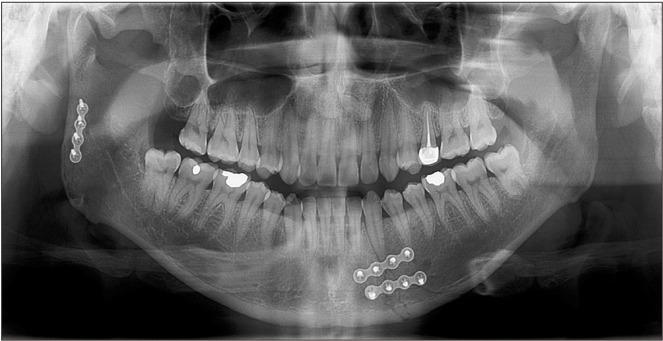

A transparotid approach, with a retromandibular or preauricular incision, is an alternative surgical approach for treating a subcondylar fracture and reducing the potential for complications such as injury to the facial nerves. However, retromandibular and preauricular incisions are both created far away from the parotid gland-dissection area. Thus, it is necessary to undermine the skin and retract it anteriorly to access the surgical field. Here, we introduce a modified approach wherein the incision allows for direct access to the fracture site. This approach may be adopted to shorten the incision length, reduce the retraction trauma at the surgical site, and help prevent injury to the facial nerve.

采用下颌后或耳前切口的透明入路是治疗髁突骨折和降低诸如面神经损伤等并发症可能性的另一种手术方法。然而,下颌后和耳前切口均远离腮腺解剖区域。因此,有必要分离皮肤并向前牵拉以进入手术视野。在此,我们介绍一种改良方法,该方法通过切口可直接进入骨折部位。可采用此方法缩短切口长度,减少手术部位的牵拉创伤,并有助于防止面神经损伤。